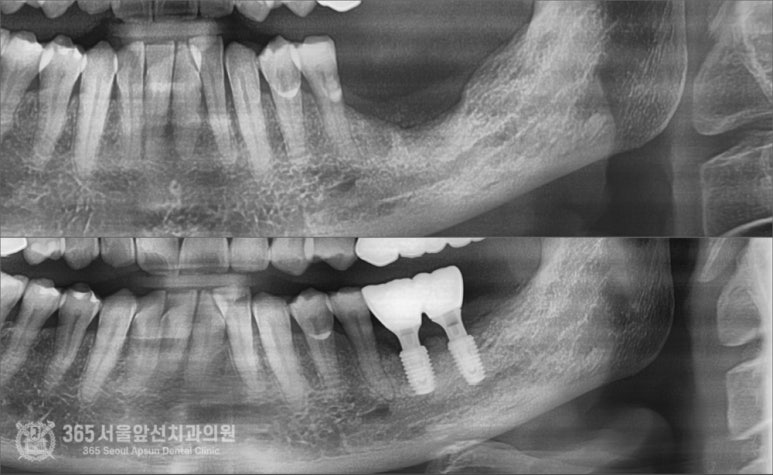

촬영일시: 2024.05.11. 처음 내원 당시 엑스레이 사진입니다. 오래전에 타치과에서 치료 받으셨던 임플란트 부위에 염증이 생겨서 뼈가 거의 남지 않은 상황입니다. 심한 불편감을 호소하셔서 일단 임플란트를 제거하기로 하였습니다.

촬영일시: 2024.07.07. 제거하고 대략 2개월 정도 지나고 엑스레이입니다. 뼈가 움푹 파여서 이 상태로는 임플란트 식립이 어려운 상황입니다. 촬영일시: 2024.08.10. 골이식과 동시에 임플란트를 식립하였고 사진의 노란색 부위만큼이 골이식이 들어간 부위입니다. 이 환자분의 증례에서 시행된 골이식술은 수직골증강술이라는 매우 고난이도 술식입니다. 하지만 숙련된 의료진과 함께라면 걱정안하셔도 되겠습니다 ㅎㅎ 촬영일시: 2024.10.10. 약 5개월 정도 지난 후 잇몸을 열어서 이식된 골이 잘형성되었는지 확인함과 동시에 임플란트도 뼈와 잘결합되었는지 확인합니다. 다행히 뼈 형성도 좋고, 임플란트도 단단하게 잘 붙었습니다 ㅎㅎ

촬영일시: 2024.05.11. / 2024.10.20. 임플란트 보철물을 완성한 후 엑스레이 사진입니다. 난이도가 높은 재수술 케이스임에도 성공적으로 마무리되었습니다. 오늘은 주안역 임플란트 재수술 증례를 소개해드렸습니다. 아무리 어려운 수술이더라도 다 방법은 있기에 너무 걱정은 안하셔도 괜찮을 것 같습니다 ㅎㅎ 앞으로도 좋은 증례로 찾아뵙겠습니다. 지금까지 365일 열린 가까운 서울대학교 치과병원을 지향하는 주안역치과 365서울앞선치과였습니다. 감사합니다. ※ 365서울앞선치과의원의 모든 포스팅은 각 진료과 의료진이 직접 작성합니다. 365서울앞선치과의원 블로그의 임상 케이스 게시물은 환자분께 의학적으로 정확하고 상세한 정보를 드리기 위해 각 진료과 의료진이 직접 작성하며, 모든 증례 사진은 본원 의료진이 직접 시술한 증례를 촬영한 것으로, 의료법 제23조, 제56조에 의거하며 환자분의 동의를 얻어 포스팅에 사용하였습니다. 또한 해당 케이스는 본 환자분의 치료 결과이며, 환자 상태에 따라 치료의 결과는 달라질 수 있습니다. |